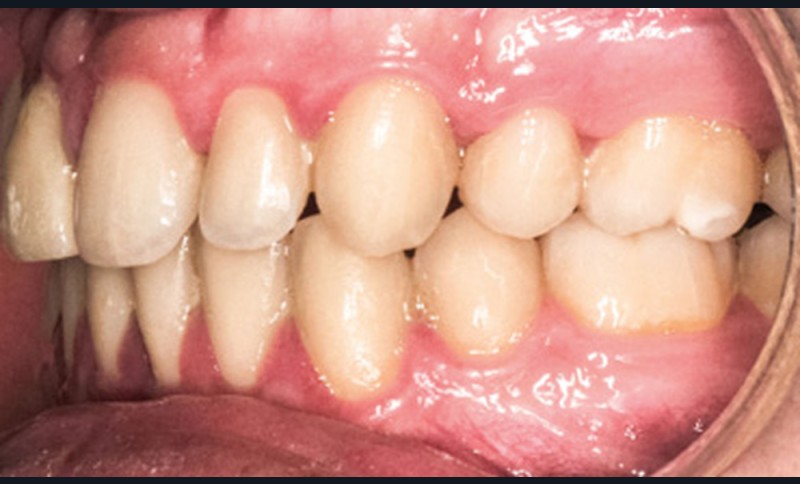

En ce qui concerne les objectifs de traitement, le profil du patient reste pratiquement inchangé avec une compétence labiale au repos (fig. 4a). D’un point de vue occlusal, la correction en classe I d’Angle est obtenue (fig. 4b-c). La difficulté résidait dans la gestion de la substitution (fig. 5) ; outre le manque d’hygiène notable due à une perte de motivation du patient sur la fin de traitement, notons une perte d’alignement de la ligne des collets en regard de 13, ainsi qu’une bosse canine toujours présente. Une correction par chirurgie parodontale permettra la symétrie du sourire et l’intégration prothétique optimale de la restauration de 11 [3] (fig. 6).